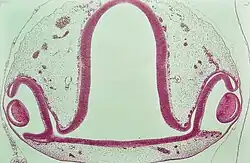

Die wohl spektakulärste Fehlbildung ist das schon erwähnte Zyklopenauge, die Zyklopie. Durch Unterbleiben des Auseinanderweichens der beiden Augenanlagen bildet sich ein Konglomerat von Augenteilen in der Mitte der oberen Gesichtshälfte (Abb.). Wegen der damit verbundenen Gehirnmissbildung sind die Feten nicht überlebensfähig. Unvollständiger Verschluss des embryonalen Augenbechers führt zu Spaltbildungen unterschiedlichen Ausmaßes, den Iris-, Aderhaut- und Netzhaut-Kolobomen. Viruserkrankungen der Mutter im ersten Drittel der Schwangerschaft, aber auch die Einnahme mancher Medikamente, können zu Entwicklungsstörungen führen. Bekannt ist die Linsentrübung neben anderen Schäden durch Rötelninfektion in der 4. bis 8. Schwangerschaftswoche, also in der Phase der Linsenentwicklung. Nicht selten sind beim Menschen persistierende Reste der Pupillarmembran als in der Regel harmlose Hemmungsmissbildung. Nur vereinzelt sind Blutungen daraus beobachtet worden. Sie sind auch bei Wirbeltieren (Ratten, Kaninchen) beschrieben.[47]